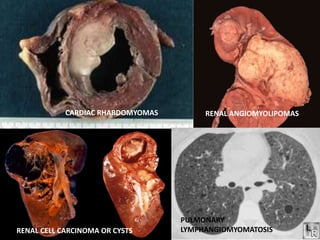

RENAL ANGIOMYOLIPOMAS

CARDIAC RHABDOMYOMAS

PULMONARY

LYMPHANGIOMYOMATOSIS

RENAL CELL CARCINOMA OR CYSTS

FACIAL ANGIOFIBROMAS ADENOMA SEBACEUMLEAF SPOTS SUBUNGUAL FIBROMAS SHAGREEN PATCHES GINGIVAL FIBROMAS

SECONDARY (PRESUMPTIVE) FEATURES FIRSTDEGREE AFFECTED CARDIAC RHABDO RETINAL HAMARTOMA ACHROMIC PATCH RENAL AML SHAGREEN PATCH FOREHEAD PLAQUE CORTICAL TUBERS ON RADIOLOGY RENAL CYSTS NON-CALCIFIED SUBEPENDYMAL NODULES PULMONARY LAM